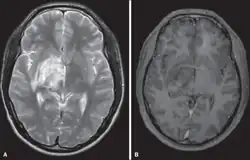

Diagnostic method | Brain/Spine magnetic resonance imaging (MRI) [2] |